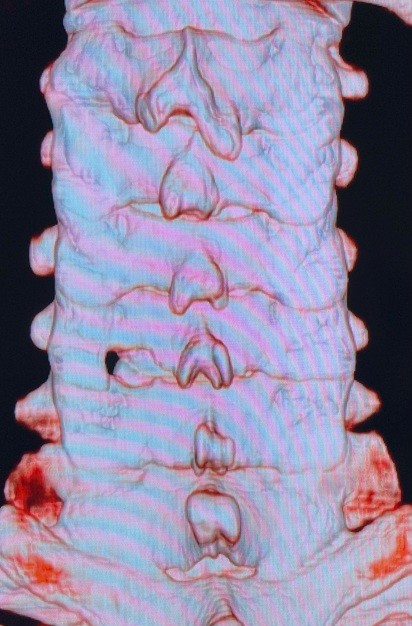

ナビゲーションシステムを用いた

スクリューを用いた手術

ナビゲーションシステムを用いたスクリューを用いた手術

ナビゲーションシステムを用いた固定術への応用